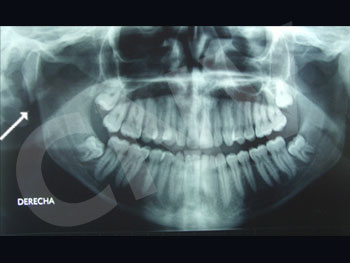

برای یک جراح فک و صورت، تشخیص نوع» شکستگی حیاتی‌ترین بخش کار است. ما معمولا شکستگی‌های ماگزیلا را بر اساس طبقه‌بندی مشهور «لوفورت» Le Fort دسته‌بندی می‌کنیم که نشان می‌دهد خط شکستگی دقیقا از کجا عبور کرده است:

شکستگی لوفورت

تشخیص دقیق نوع شکستگی لو فورت فقط با سی‌تی اسکن سه‌بعدی امکان‌پذیر است و طرح جراحی بر اساس آن ریخته می‌شود. برای دریافت اطلاعات بیشتر در مورد انواع شکستگی لوفورت و جراحی ارتوگناتیک به این صفحه مراجعه کنید.